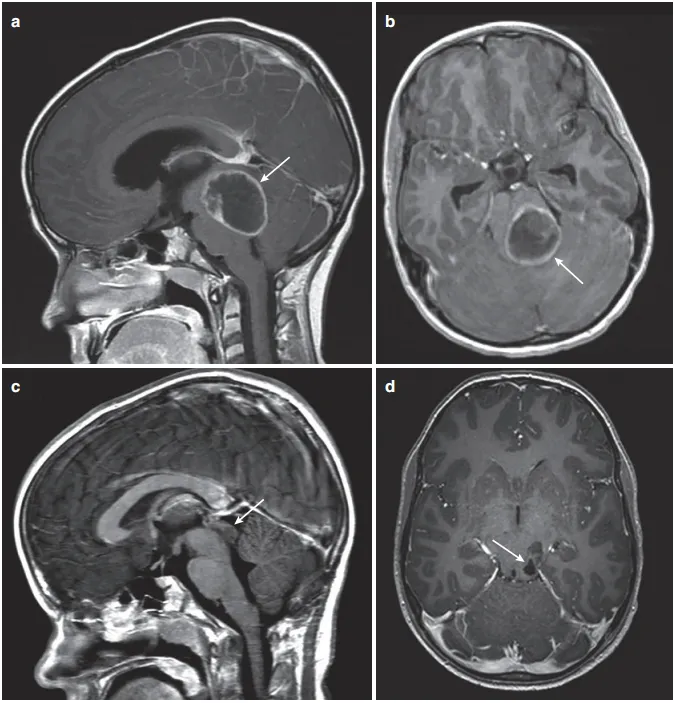

图2:(a)矢状位增强T1 MRI显示巨大后颅窝囊性病变,肿瘤中心于顶盖区(箭头)。(b)增强MRI显示顶盖和第四脑室受累程度(箭头)。(c)后颅窝开颅、肿瘤囊肿引流、囊肿囊被清除后,在MRI增强(箭头)上仅能看到小的顶盖变形。(d)术后增强MRI显示肿瘤起源于顶骨区,无占位效应(箭头)。